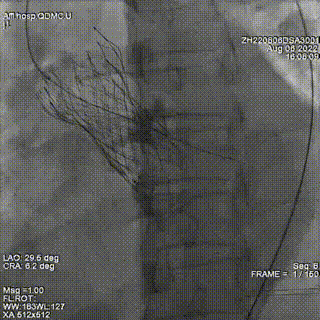

结合术前CTA评估,在S曲线中确定左冠切线位投照角度为LAO32 CRA6, 并在此角度下通过DSA引导导丝通过PVL。